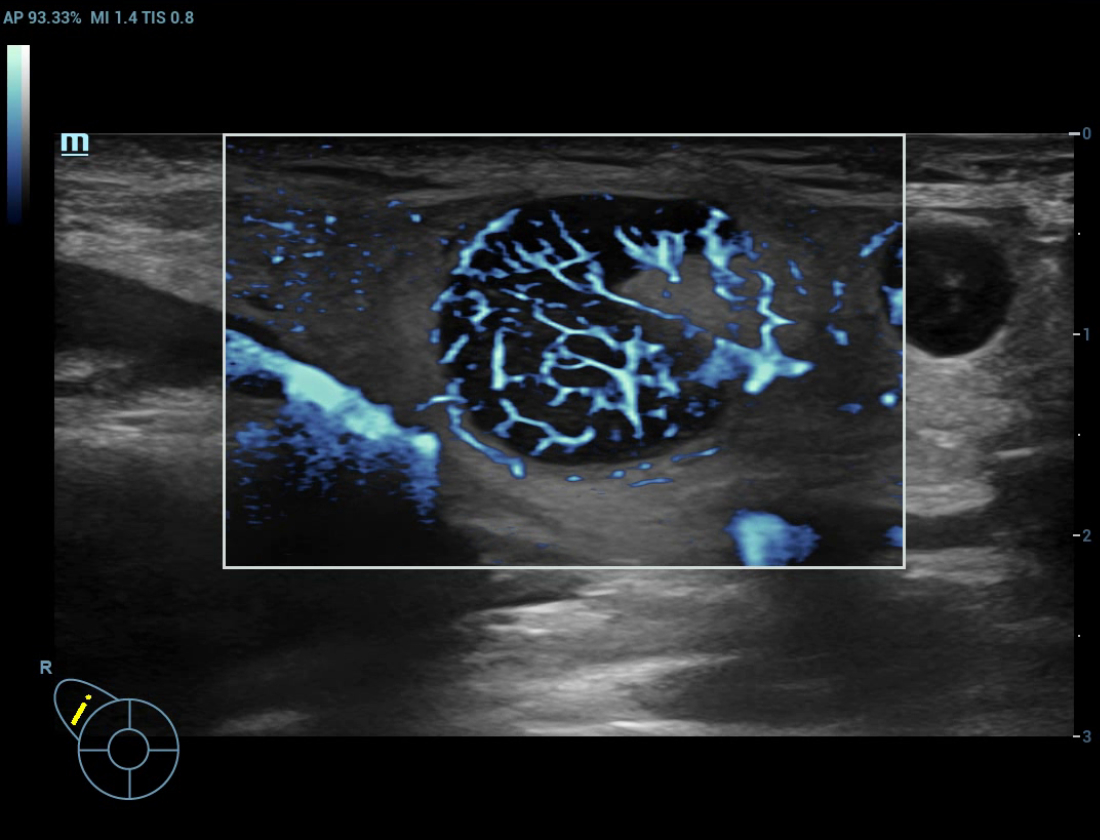

Ultra Micro Angiography (UMA)

UMA migliora la sicurezza diagnostica ampliando la visibilitĂ dei flussi sanguigni fino al livello dei vasi piĂč piccoli, con una sensibilitĂ e una risoluzione superiori.

Massa mammaria pUMA

Massa mammaria cUMA

Massa mammaria